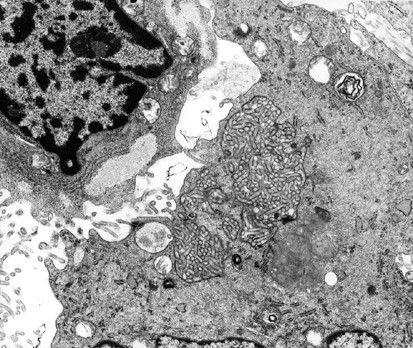

Figure 6

The mesothelioma cell on the right shows early development of what appears to be an intracytoplasmic lumen that is occupied by a profusion of microvilli, while the cell on the left shows small lakes of intracytoplasmic glycogen (× 15 200).